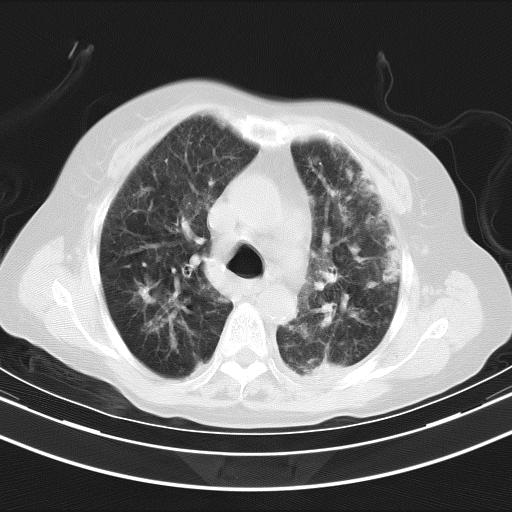

老年女性,嗜睡3天,意识模糊。轻咳,无发热。

两肺慢支炎伴感染,左侧胸腔积液。纵膈及双侧肺门淋巴结肿大建议复查。

双肺多发淡片影,毛玻璃影,,支持支气管肺炎,,建议血气找原因,,嗜睡是否肺性脑病?有没有慢支病史?

双肺炎症,建议抗炎治疗后复查,见过几个老年肺炎病例,没有发烧、咳嗽症状,直接以昏迷就诊。

1)两肺感染性病变;建议抗炎治疗后复查。2)纵隔淋巴结肿大。3)左侧胸腔积液。